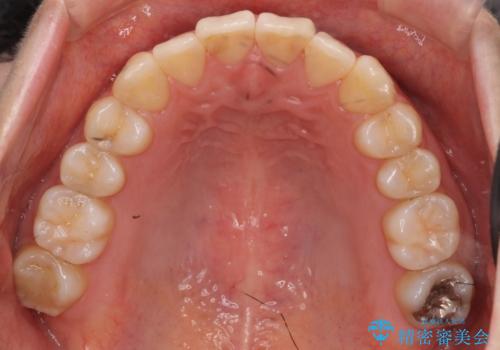

軽度の前歯のがたつき 下の前歯が生まれつき少ない

- 前歯のがたつきを主訴に来院。

下の前歯が生まれつき3本でした。

そのため、上の前歯が少し余るような形で出っ歯になっていたため、スペースを作って引っ込めています。

下を3本でそのまま並べてあるため、上下の正中は合いません。

合わせようとすると抜歯か、下の隙間を無理やり開けてブリッジとなりますが、そこまでするメリットがないため、下はそのままの歯の数を生かしています。